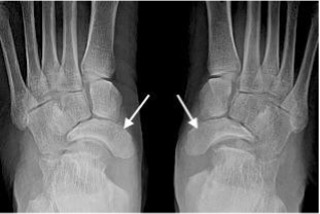

Freiberg’s disease

- Usually the second or third metatarsal heads

- Flattening and sclerosis of the metatarsal head

- Widening of the joint space due to the ‘eggshell crush’ degeneration of the metatarsal head

- May result in secondary osteoarthritis

Freiberg’s disease with flattening and sclerosis of the 2nd metatarsal head (arrow)